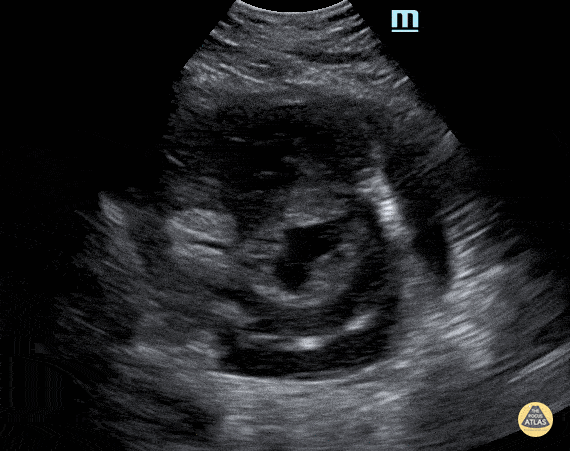

Peds-Cardiac - PSSA with moderate effusion

Teenage female with COVID-associated pericarditis with moderate effusion. Contributor: Peter Gutierrez, MD, FAAP, Emory University School of Medicine/Children's Healthcare of Atlanta, @pocuspete